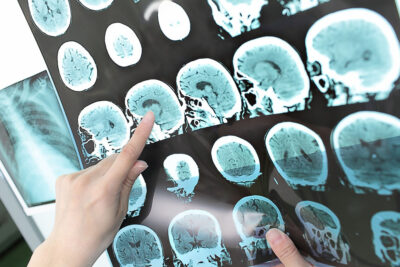

Multiple sclerosis (MS) can be symptomatic at any age but most often is diagnosed between the ages of 20 and 40 years, making it a common neurological condition among young adults.

In this study, Knowles at al used the United Kingdom (UK) Multiple Sclerosis Register Database and the United Kingdom MS Tissue Bank to retrospectively examine patients with late-onset MS (LOMS; symptom onset older than 50 years of age) and those with early onset MS (EOMS; onset between ages 18 and 49 years). Within the entire cohort of 17,124 patients with MS, 1,608 (9.4%) patients were identified as having LOMS. When compared to EOMS, the LOMS cohort had a lower percentage of female patients, a higher proportion of primary progressive MS, and a lower proportion of relapsing-remitting MS. Ambulation changes, compared to visual symptoms or numbness, were more often among the self-reported symptoms in the LOMS population. Also, the degree of disability at the time of diagnosis was worse in patients with LOMS compared to patients with EOMS.

Cortical lesions constituted a larger proportion of the total lesion load in LOMS. Neuronal density was decreased in the cingulate and thalamus in the LOMS group when compared to the EOMS group. Also, LOMS patients were less likely to have actively demyelinating lesions and exhibited less leptomeningeal inflammation, while demyelination was more pronounced in EOMS.